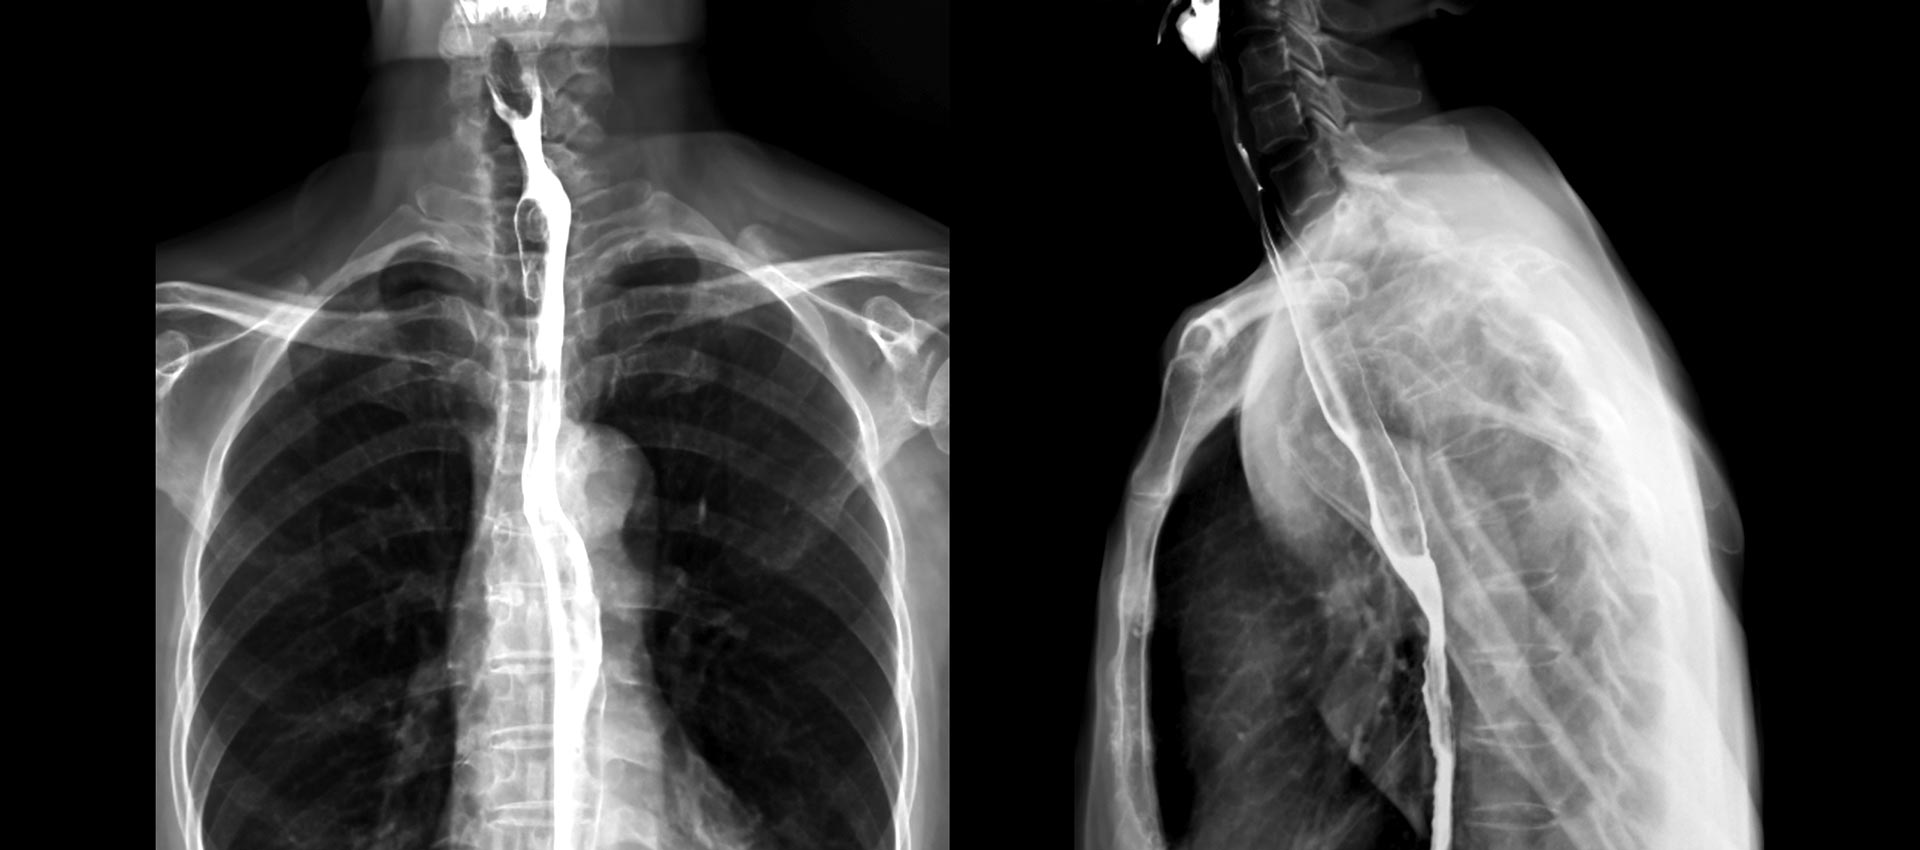

Fluoroscopy is a specialized imaging technique that provides real-time, moving images of the body using X-ray technology. Unlike standard imaging exams, fluoroscopy allows physicians to observe structures and function as they happen—often with direct physician involvement during the procedure.

Common fluoroscopic exams include:

Esophagram (barium swallow)

Upper GI studies

Small bowel follow-through

Barium enema

Intravenous pyelogram (IVP)